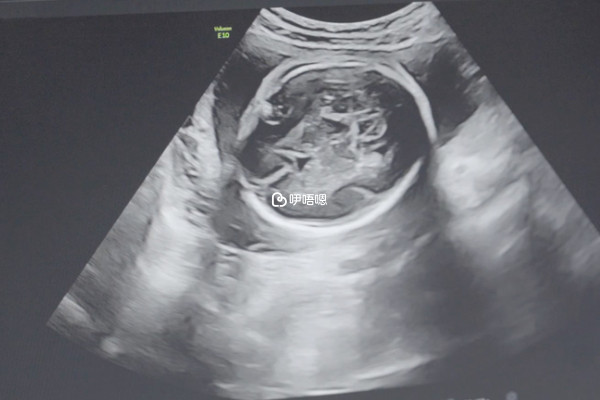

- 還可以通過B超的方式去檢驗孩子的性別,這一方法主要是掃描寶寶的生殖器官,不過可能會因為孕周不足,胎兒發育不完全或者檢查不配合,產生誤差;